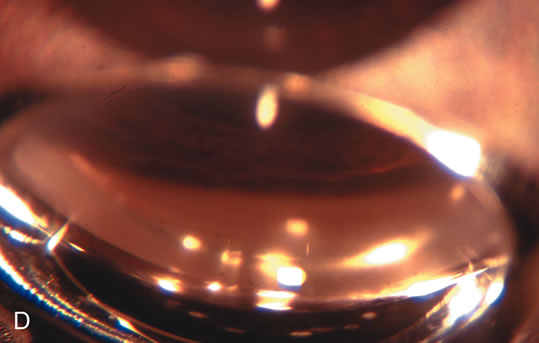

Fig. 5. Anterior chamber angle changes associated with lens extraction and PCIOL This 65-year-old Vietnamese woman has a long-standing history of chronic angle-closure glaucoma treated with laser peripheral iridectomy. The optic nerve demonstrated mild glaucomatous damage and IOP was moderately controlled on two antiglaucoma medications. The cataract was removed through temporal clear corneal phacoemulsification with foldable acrylic IOL. A. Symptomatic cataract in narrow-angle glaucoma eye with patent iridectomy. B. Intraoperative goniophotograph showing crowding of angle with increasing narrowness due to phacomorphic component. C. Intraoperative photograph showing temporal clear corneal approach with IOL in the capsular bag. D. Intraoperative goniophotograph demonstrating deepening of chamber angle following lens extraction. Proposed theories for IOP reduction following lens extraction with complete wound closure:

CATARACT EXTRACTION ALONE REDUCES IOP IN MOST EYES WITH ANGLE-CLOSURE GLAUCOMA

Uncomplicated cataract extraction substantially reduces IOP, along with the number of postoperative glaucoma medications in eyes with angle-closure glaucoma.146,147 When preoperative gonioscopy reveals PAS, along with adjacent areas of appositional closure, lens extraction alone in select cases may be a reasonable alternative to filtration surgery.148,149 Phacomorphic angle-closure disease due to enlargement of the lens with progressive angle crowding is eliminated following lens extraction. The width and depth of the anterior chamber angle in eyes with angle-closure glaucoma increases significantly after cataract extraction with IOL implantation and becomes similar to open-angle glaucoma and normal eyes.150,151 (Fig. 5). Combining phacoemulsification, IOL implantation, and limited goniosynechialysis is effective in the treatment of cataract and chronic angle-closure glaucoma.152 Phacoemulsification with implantation of a foldable IOL is more effective in reducing IOP and improving visual acuity than surgical peripheral iridectomy in eyes with acute angle-closure glaucoma.153